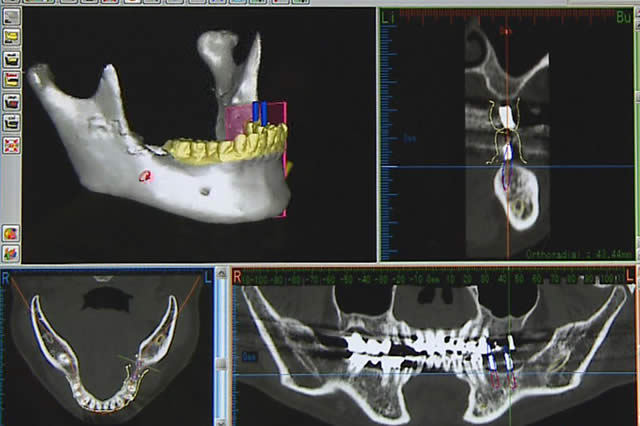

歯科用CTを使用し、お口の詳細な検査を行ないます(歯周病等がある場合は、治療を行い健全な環境に整えます)。

歯科用CTを使用し、お口の詳細な検査を行ないます(歯周病等がある場合は、治療を行い健全な環境に整えます)。

口腔内分析ソフトのiCATで、事前に手術前シミュレーションを行った後にインプラントを埋め込みます。その後、仮歯をお付けして噛合わせや状態を確認します。

口腔内分析ソフトのiCATで、事前に手術前シミュレーションを行った後にインプラントを埋め込みます。その後、仮歯をお付けして噛合わせや状態を確認します。

大学病院の口腔外科にて、腫瘍の手術やあごの骨の手術経験がある医師です。更に、当医院で使用しているCT・3D撮影により、手術前にいろいろな角度から立体的に口腔内を確認することもできるため、大変安全性が高くなっています。どうぞご安心ください。